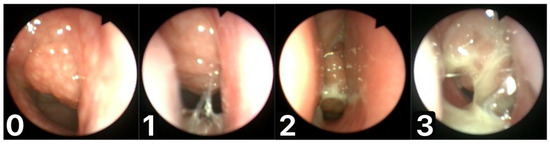

We devised a scale for assessing the mucus coverage of the adenoid, called the Mucus of Adenoid Scale by Nasopharyngoscopy Assessment (MASNA), which describes the amount of mucus covering the tonsil on a 4-point scale (0—no mucus, 1—residue of clear watery mucus, 2—some amount of dense mucus, 3—copious thick dense mucus) (Figure 1). The degree of seasonal change in adenoid mucus on the MASNA scale was compared for the total number of patients and between the designated groups. An increase in mucus coverage was represented by an increase in the degree of scale, while a decrease in the degree of scale implied reduced mucus coverage.

Figure 1.

Mucus of Adenoid Scale by Nasopharyngoscopy Assessment (MASNA): (0)—no mucus; (1)—residue of clear watery mucus; (2)—some amount of dense mucus; (3)—copious thick dense mucus.